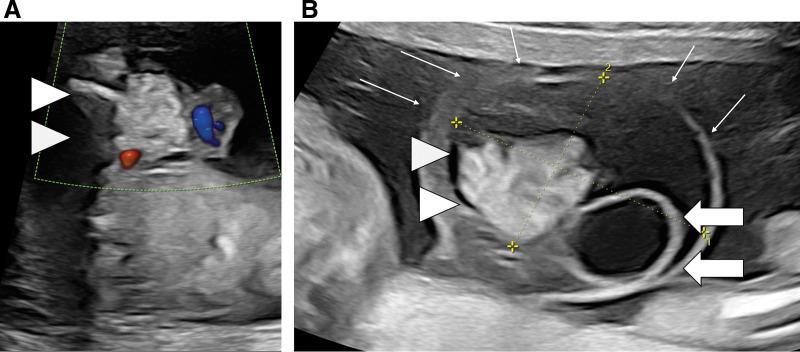

A male infant was delivered via caesarean section at 36 weeks of age, with ruptured membranes and cloudy amniotic fluid. Fetal ultrasonography at 16 weeks had previously revealed an omphalocele with intestinal prolapse, and at 20 weeks, an umbilical cord cyst was suspected. At birth, the herniation sac ruptured, and abdominal wall closure and cyst excision were performed. The cyst, initially thought to be umbilical in origin, was instead identified as a hepatic cyst connected to the liver. Pathological examination confirmed the diagnosis. The infant was further diagnosed with Beckwith-Wiedemann syndrome, and was ultimately discharged 32 days postoperatively, with no recurrence to date.

一名男婴在36周时通过剖宫产出生,胎膜破裂,羊水浑浊。16周时的胎儿超声检查先前发现有脐膨出伴肠脱垂,20周时怀疑有脐带囊肿。出生时,疝囊破裂,进行了腹壁闭合和囊肿切除。最初认为起源于脐带的囊肿,实际上被确定为与肝脏相连的肝囊肿。病理检查确诊。该婴儿进一步被诊断为贝克威思-维德曼综合征,最终术后32天出院,至今无复发。